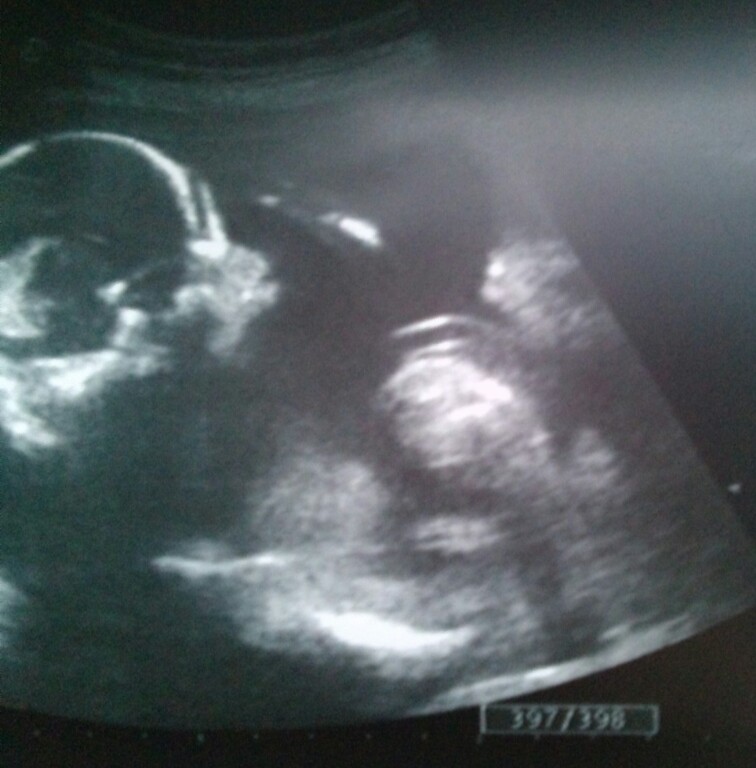

Attachment 18676 Please have a look! What do you think, girl or boy?? Thanks a lot!!

sorry at this stage you need a potty shot...